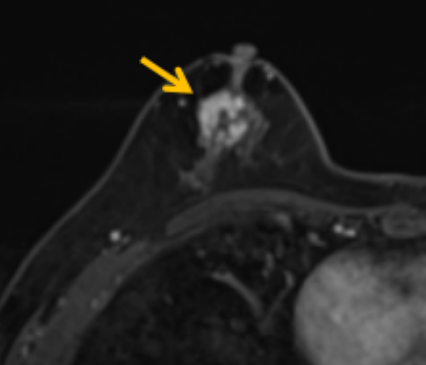

陳寶瑩評(píng)估圖像后發(fā)現(xiàn)病變?yōu)閮H僅在磁共振增強(qiáng)時(shí)顯示,為非腫塊樣病變,比較散,必須取得足夠多的組織才能確保病理檢查的準(zhǔn)確性,常用的核芯針活檢獲取的組織較少,因此最終確定了磁共振引導(dǎo)下行真空輔助抽吸旋切活檢。取得患者及家屬認(rèn)可后,陳寶瑩帶領(lǐng)團(tuán)隊(duì)開始進(jìn)行術(shù)前準(zhǔn)備。

針對(duì)患者乳房小固定難度大這一問題,陳寶瑩通過巧妙體位和固定器的調(diào)整,順利固定好乳房。經(jīng)過磁共振多模態(tài)掃描,陳寶瑩找出病變活性成分相對(duì)集中區(qū)域,精準(zhǔn)確定穿刺路徑,置入引導(dǎo)針、旋切針,到位后多角度旋切取出足量組織,拔除旋切針后即時(shí)行磁共振掃描,精準(zhǔn)取得組織且術(shù)區(qū)出血很少,遂加壓包扎,整個(gè)過程非常順利,旋切活檢后患者回家休息。兩天后隨訪,李女士沒有任何不適,五天后皮膚上幾毫米的小切口已經(jīng)愈合。最終病理結(jié)果證實(shí)為乳腺導(dǎo)管原位癌,為早期乳腺癌,為患者后續(xù)針對(duì)性治療奠定了基礎(chǔ)。